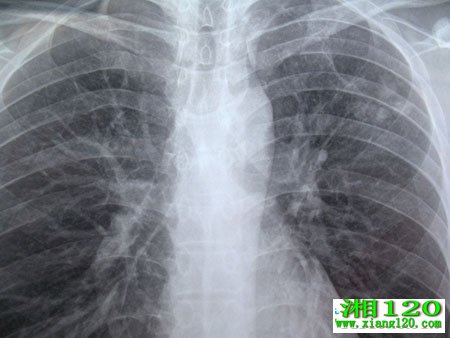

当出现以上症状时,人们应去医院做系统的检查。比如拍片痰涂片查结核菌、胸部X线检查等。医生根据检查结果,综合判定确诊。,以下人群都属肺结核高发人群,应定期体检:就是与肺结核病人密切接触者;是患有糖尿病及术后的病人;第三是长期应用肾上腺皮质激素免疫抑制剂的病人;第四是久治不愈的感冒、咳嗽、发热,以及肺部有阴影者,经正规治疗后仍不见好转时,应想到患结核病的可能,做进一步的检查。